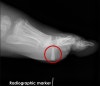

Lateral view : Use of a second image shows the foreign body is within plantar-side soft tissues.

Note the radiographic marker which has been used to show the point of breach in the skin.